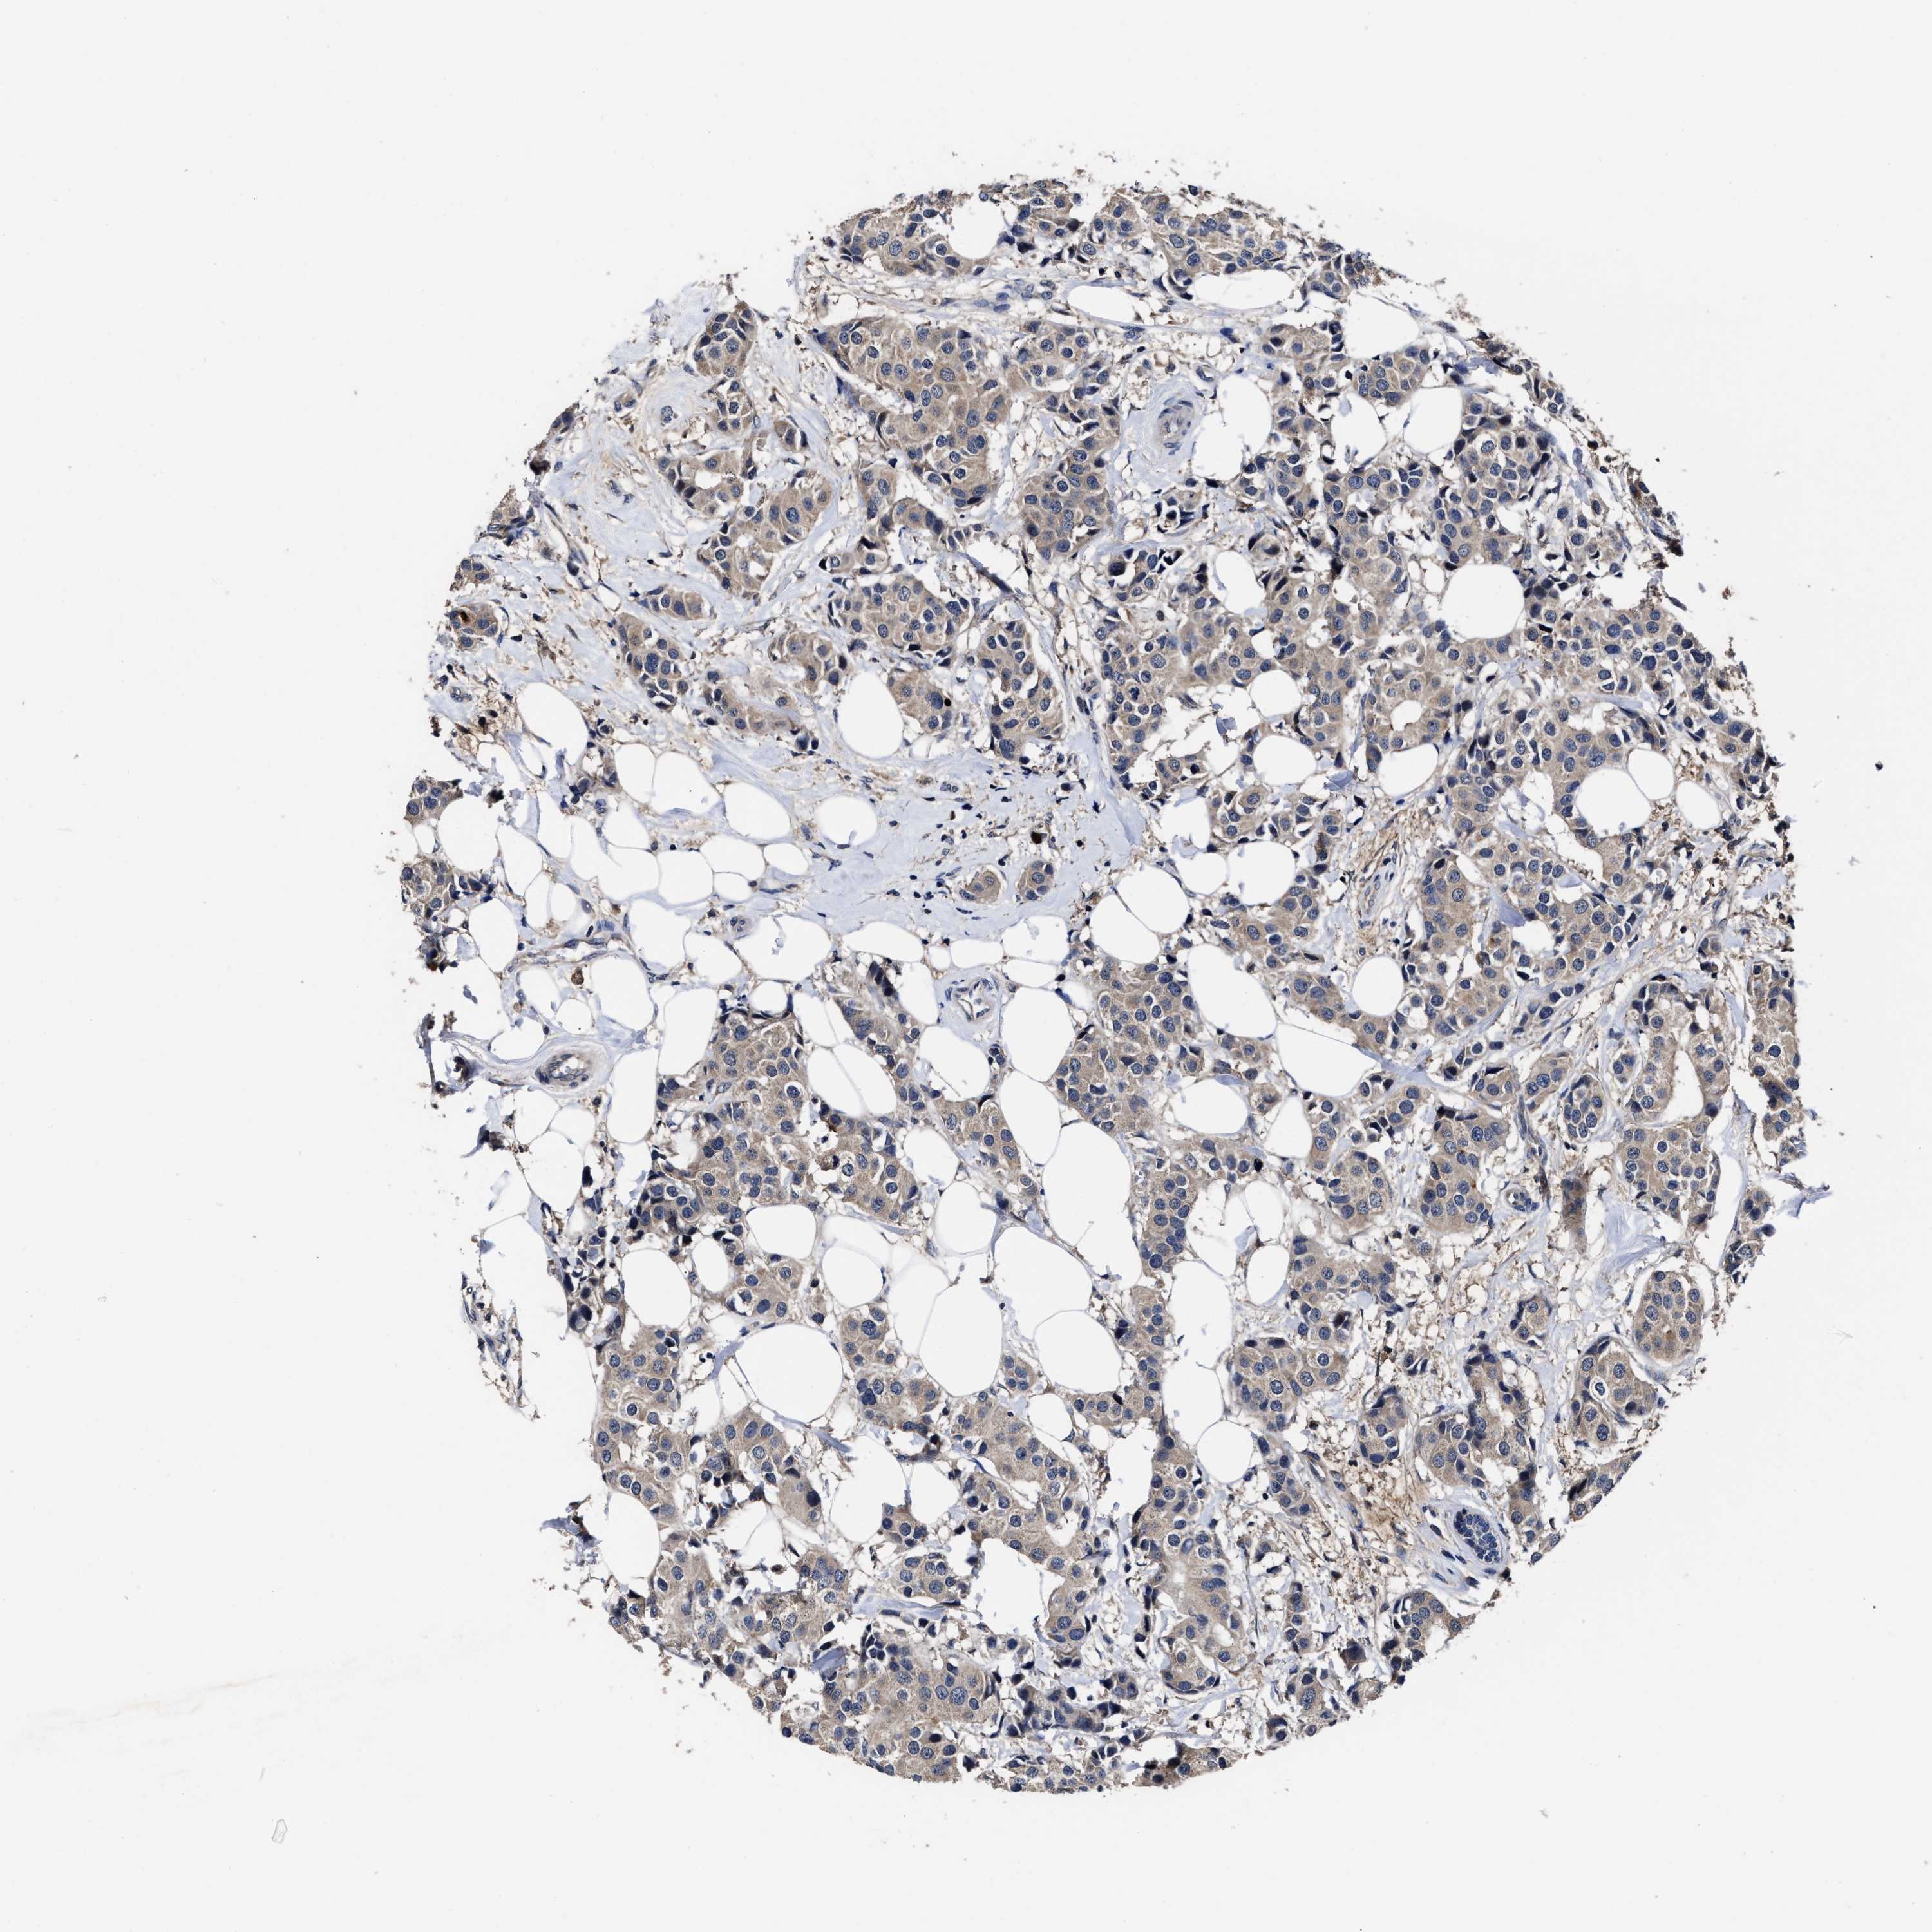

CANCER BREAST CANCER Show tissue menu

BRCA TCGA BRCA VALIDATION PROTEIN EXPRESSION